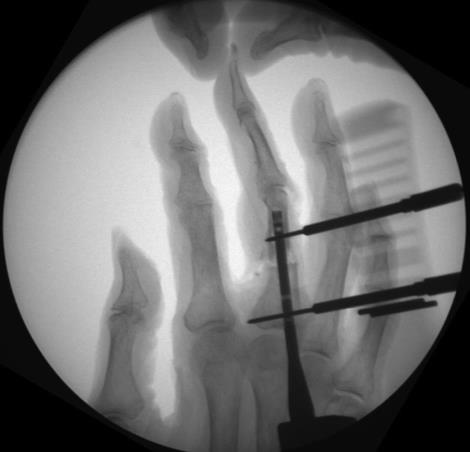

• Phalanx

• fully flex the metacarpophalangeal joint mark the dorsal third of the metacarpal head

• expose the base of the proximal phalanx by subluxing to allow percutaneous access to the proximal articular surface

• the illustrated surgical technique uses an antegrade approach, described as less traumatic to the PIP joint

• retrograde approach is still possible

• Phalanx Technique

• Primary Steps

• step 1

• insert a 1.6mm k-wire into the subluxed proximal phalanx base in line with the medullary canal of the proximal fragment

• advance the k-wire to the fracture site under fluoroscopy, reduce the fracture, and advance the k-wire into the proximal phalanx head

• determine nail length with a measurement ruler or depth gauge and subtract 10mm from the length reading

• account for the proximal and distal nail ends being 5mm each from the articular surfaces